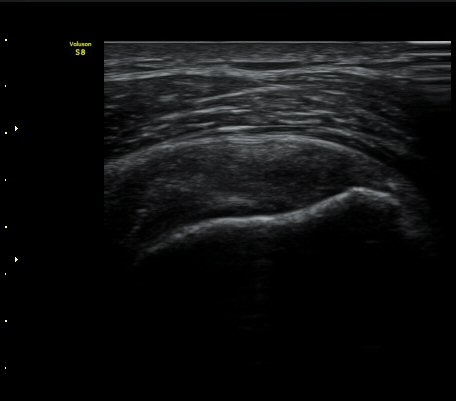

±Ø»ó°Ç Ⱦ´Ü¸é°Ë»ç½Ã ±Ø»ó°Ç ÀϺΠÀú¿¡ÄÚ ºÎÁ¾°ú ¹Ì¼¼ÇÑ °Ç ¿¬°á¼º ¼Ò½ÇÀÌ °üÂûµÊ(±×¸² 4, 5).

±×¸² 4)¿¡¼­ °üÀý¿¬°ñ°æ°è¸é ¡ÈÄ(articular interface sign)°¡ °üÂûµÊ.